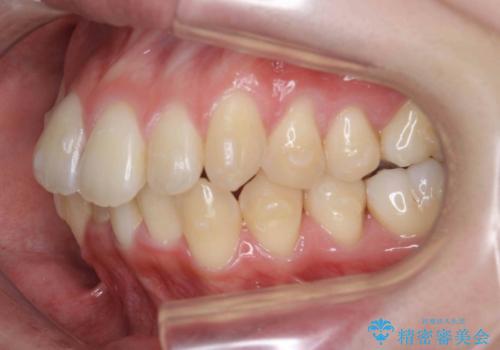

前歯のがたつきをマウスピース矯正できれいに!

- 目立つ前歯のがたつきを改善したい、と矯正治療を希望され来院されました。

今回の治療ではシミュレーションでしっかりと検討した結果、下顎は前歯を1本抜去し仕上げる治療計画としました。